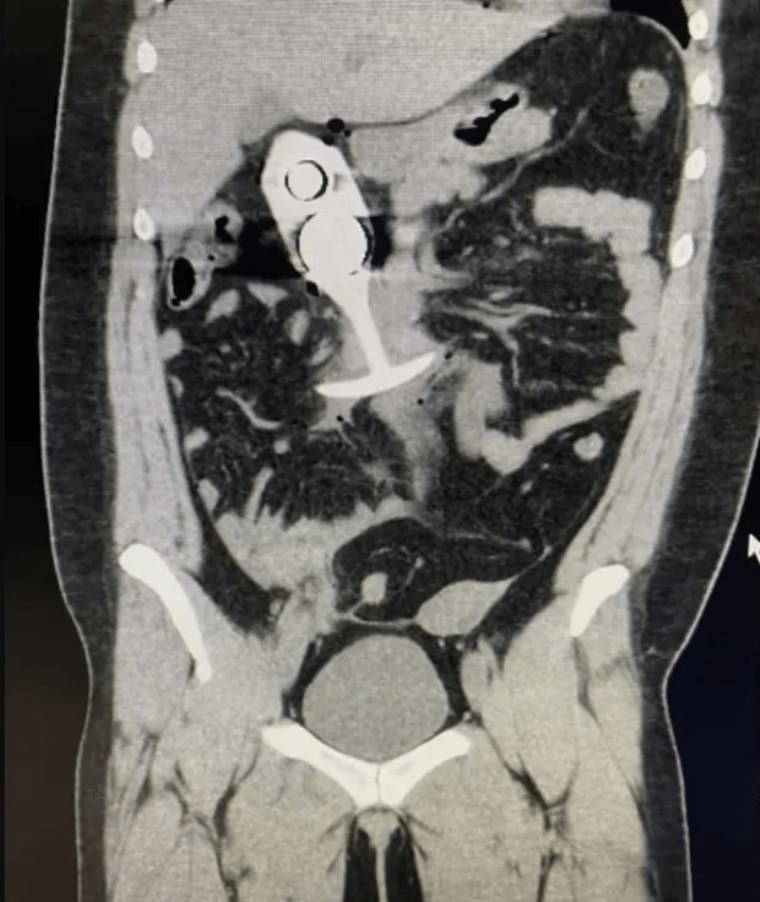

İngiltere'de 22 yaşında bir kadın, MR taramasına vücudunda bulunan bir seks oyuncağıyla girdi. Tarama sırasında manyetik alan tarafından yukarı çekilmesiyle kadın ciddi şekilde yaralandı. Olay, tarama öncesinde oyuncakta metal bulunduğunu bilmediği için yaşandı. Yüzde 100 silikon olduğunu düşündüğü seks oyuncağı makatında taramaya giren genç kadın, oyuncağın çekirdeğinde metal bulunduğu anlaşılınca büyük tehlike yaşadı.

Taramadan sonra, hasta şiddetli ağrı hissetti ve bilincini kaybedecek kadar kötüleşti. Oyuncak, hastanın vücudunun alt kısmından yukarı doğru hareket ederek ciddi iç yaralanmalara neden oldu. Sağlık ekipleri tarafından hemen hastaneye kaldırılan kadın, ciddi yaralar almasına karşın hayati tehlikeyi atlattı.